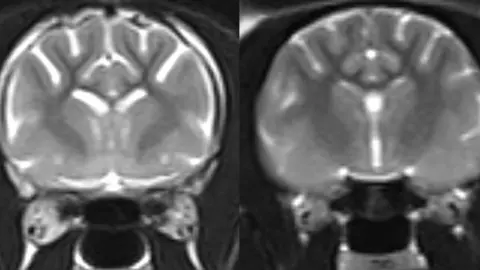

Microscopy images of older cats which had previously shown symptoms of feline dementia revealed a build-up of amyloid-beta within the synapses – the junctions of brain cells.

Synapses allow the flow of messages between brain cells, and losing these causes reduced memory and thinking abilities in humans with Alzheimer’s.

The researchers found evidence that brain support cells – called astrocytes and microglia – engulfed the affected synapses.

It’s known as synaptic pruning, an important process during brain development but which contributes to dementia.